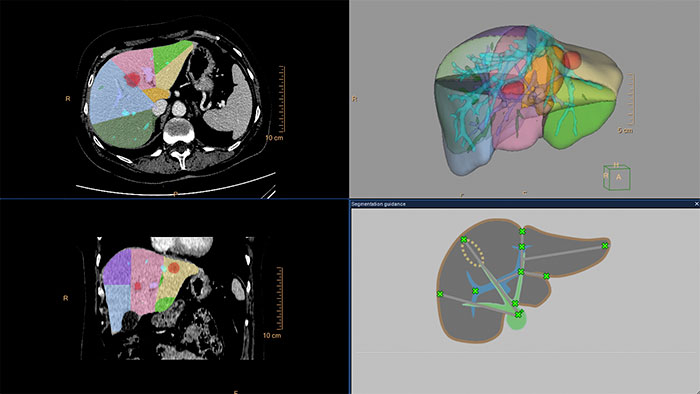

Advanced Liver segmentation

Automatically identifies, segments and quantifies the liver from the portal venous phase of a tri-phase liver scan and classifies the hepatic and portal veins.

Streamlined modeling workflow

Allows to view volumetric images of anatomical structures, perform segmentation, edit and combine segmented elements (tissues) into a 3D model.